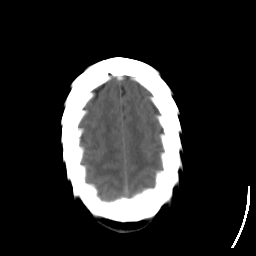

Stroke CT #2 -- Slice #21

[Home][Help][Clinical] Slice 21